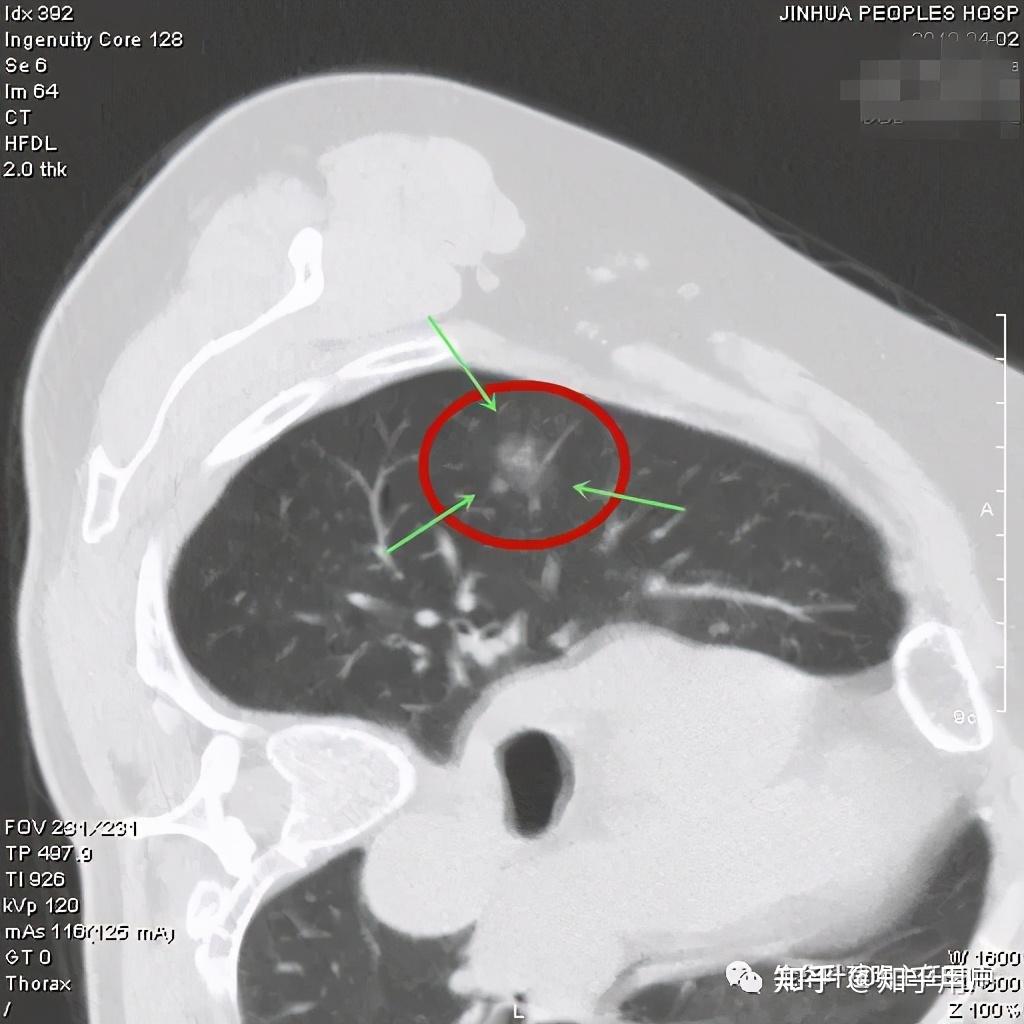

距离做肺部CT到现在,时间过去了25天,期间了解了有关磨玻璃结节的很多知识,也在知乎发了帖,得到很多小伙伴的建议,让我感受到温暖和力量。十分感谢!

准备好裁剪好的CT图,可医院给刻录的光盘,将信将疑地注册了好大夫账号。综合了百度的结果和网友推荐的情况,最终挂了孙希文的问诊号,选的图文问诊。

昨天下午问的,昨晚就得到了医生肯定的回答——“原位癌”

孙主任给的结果是混杂性结节,原位癌。至于手术建议,说的是:“现在手术省心了;以后手术有一点点风险,怕会慢慢长大,一般涨到8mm需要很多很多年。”